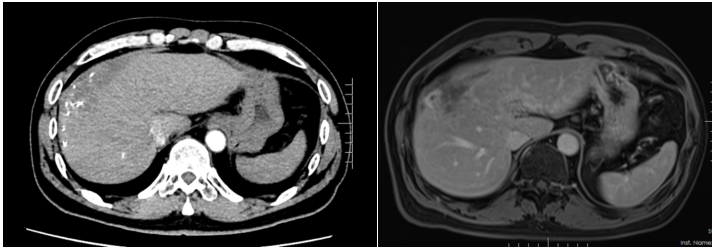

患者入院时诉说了自己与晚期肝癌对抗的痛苦与不易,同时也表明了与病魔抗争到底的决心。入院后,龙奎副主任医师立即为患者完善了CT、MRI+MRCP,ICG等检查,经过术前多学科MDT讨论后,认为患者肝癌转化效果满意,可以手术治疗。

由于患者肝癌位置特殊,肿瘤占据肝脏多个亚段,并且门静脉伴有海绵样变,手术中出血风险较大。另外,如大范围切肝,残余健全肝脏较少,术后有肝功能衰竭风险。为了保证患者手术质量安全,肝胆胰外科三病区高度重视,龙奎副主任医师组织科室详尽讨论了患者手术方案,在老专家孙敏教授、滕毅山教授、莫小华教授的鼎力支持下,最终决定采用腹腔镜微创手术方式完成手术,以最小的创伤让患者获得最大的收益。

手术中,由于患者有门静脉海绵样变特别容易出血,转化治疗后肝内管道走行变异,手术过程尤其艰难。龙奎副主任医师、董文志副主任医师、孙翊程医师与华人色情 优秀的麻醉团队、手术室护士团队通力合作,利用医院先进的荧光腹腔镜导航辅助,精准地完成了腹腔镜下肝IVb段+V段+胆囊切除术,历时5个小时,出血量200ml。